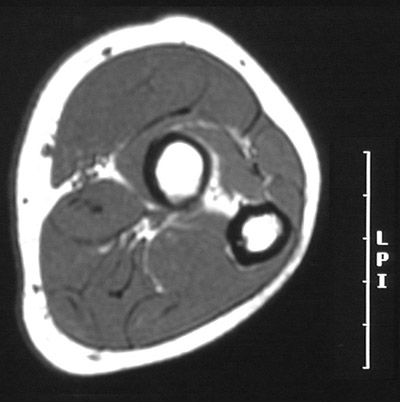

This is a normal axial T1 weighted MRI scan demonstrating the Radius, marrow cavity and Compact or cortical bone and Ulna and Interosseus membrane and Anconeus and Extensor carpi ulnaris and Extensor digitorum communis and Extensor carpi radialis brevis and Extensor carpi radialis longus and Supinator and Brachioradialis and Pronator teres and Flexor carpi radialis and Palmaris longus and Flexor digitorum superficialis and Flexor carpi ulnaris and and Flexor digitorum profundus.